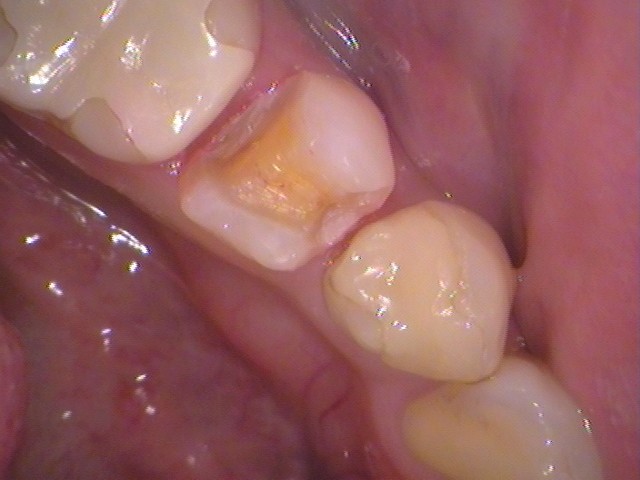

お口の中を見てみると、奥歯に白い詰め物が入っています。

こちらの治療した歯が気になるところです。

見た目で浮いているように見えます(^^;

外してみると、内部には虫歯は無く歯の状態は問題ありませんでした。

詰め物が合っていなく、歯をズレていたため、フロスが引っ掛かっていたようです。